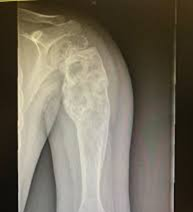

1. Rayos X

2. Resonancia magnética

3. TAC contrastado

4. Gammagrafía Ósea

Se usa una amplia gama de técnicas de adquisición de imágenes para poder ver dentro del cuerpo y determinar el alcance de un sarcoma óseo y establecer la presencia o ausencia de enfermedad metastásica distante.